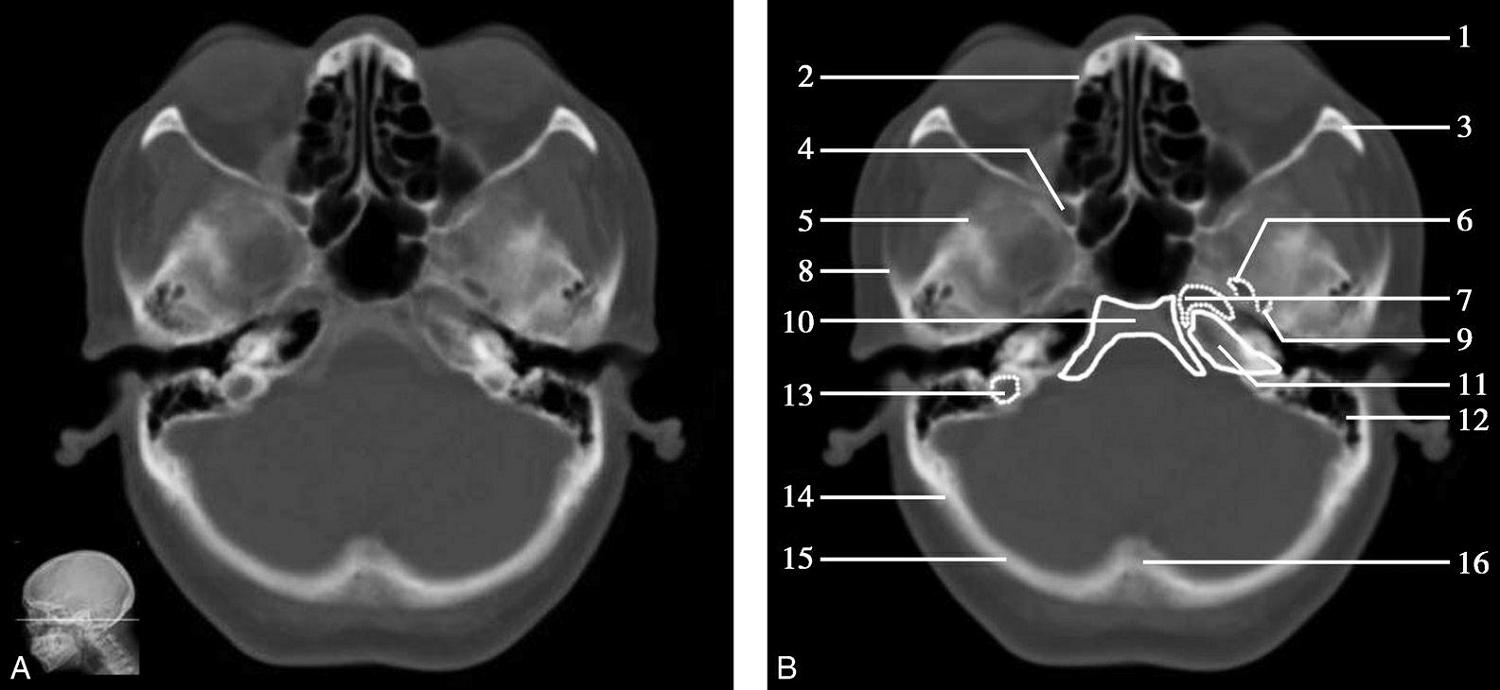

重要结构:视交叉、尾状核头、额叶、颞叶、外侧裂池(图1-2-52、图1-2-53)。

图1-2-52 视交叉层面

A.冠状面;B.冠状面标注

1.上矢状窦;2.大脑镰;3.额叶;4.扣带回;5.胼胝体体部;6.侧脑室前角;7.尾状核头部;8.内囊前肢;9.透明隔;10.豆状核;11.隔核;12.伏隔核;13.视交叉;14.鞍上池;15.外侧裂池;16.前床突;17.颞叶;18.海绵窦;19.蝶窦

图1-2-53 视交叉层面(骨窗)

1.矢状缝;2.顶骨;3.顶颞缝;4.前床突;5.颞骨;6.蝶鳞缝;7.蝶窦;8.颧弓;9.翼突内侧板;10.翼突外侧板

此层面正中线上部有大脑纵裂池及其内的大脑镰,大脑镰的上端与上矢状窦相连,下端毗邻胼胝体体部,胼胝体纤维连接双侧额叶。双侧额叶的外侧面,自上而下有额上回、额中回及额下回。胼胝体体部上方大脑镰的两侧有扣带回及扣带沟。胼胝体体部下方正中是透明隔,其两侧近似三角形为侧脑室前角,侧脑室前角顶壁为胼胝体,内侧壁上部为透明隔,底壁由隔核与伏隔核组成,外侧壁为尾状核头部。尾状核头外侧依次为内囊前肢、豆状核、外囊及屏状核。内囊位于尾状核头的外下方,是大脑皮质与皮质下中枢间的上下行纤维组成的投射纤维的主要通路。豆状核位于内囊的外下方,分为内侧的苍白球及外侧的壳核。胼胝体嘴部下方自上而下依次为大脑纵裂池、视交叉、鞍上池。视交叉两侧外下方为前床突的骨性断面,前床突内下方为海绵窦,其内可见颈内动脉断面,前床突外侧为两侧颞叶,两侧额叶与颞叶借外侧裂池分隔,额叶位于外侧裂池上方,颞叶位于外侧裂池下方。海绵窦下方中线区为蝶窦,蝶窦下方中部为鼻腔,鼻腔两侧为颞下窝。